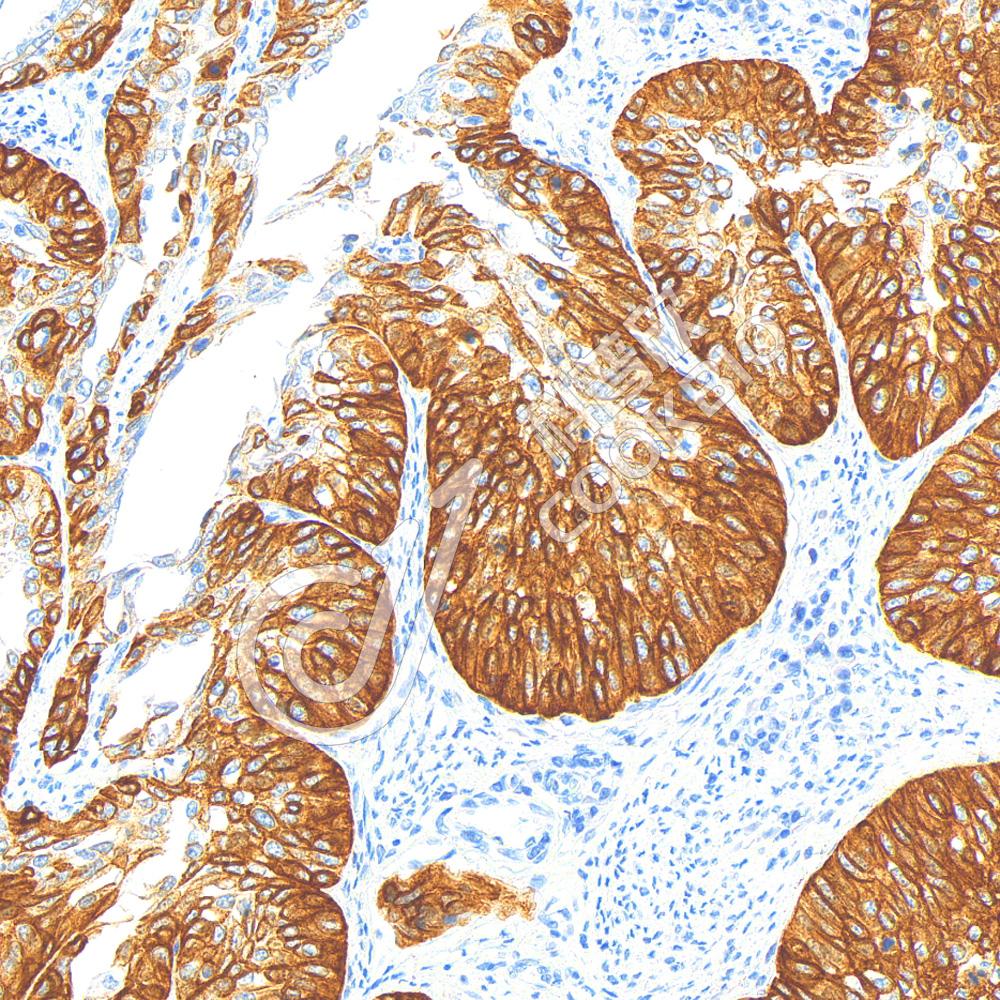

IHC检测Cytokeratin 17蛋白(货号 K2366312).

样品: 人宫颈癌, 4%多聚甲醛 (货号KSG1101) 固定12-24小时.

抗原修复: 柠檬酸抗原修复液(干粉, pH 6.0) (KSG1201), 高压锅均匀喷气计时2分钟.

—抗: 1: 1000稀释, 4℃ 孵育过夜.

二抗: S-vision免疫组化多聚二抗(山羊抗小鼠), 即用型(货号KB3903), 室温孵育20分钟.

样品: 人宫颈鳞状细胞癌, 4%多聚甲醛 (货号KSG1101) 固定12-24小时.